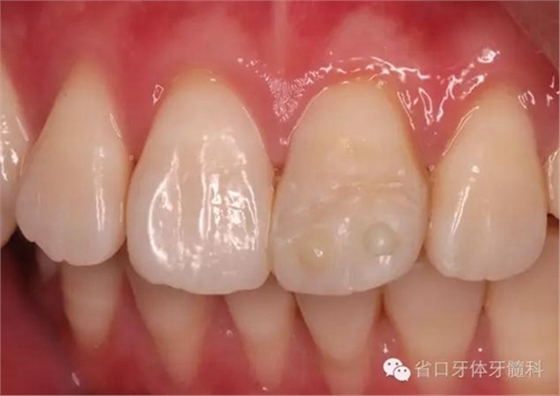

斷冠

折斷之牙體嚴(yán)重脫水,呈白堊色,斷端對(duì)位后吻合度較好,僅少許牙體缺損。